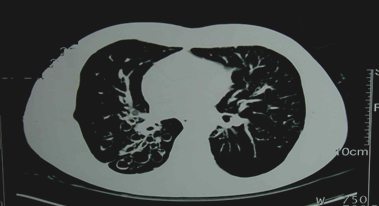

②胸部CT

可显示管壁增厚的柱状扩张或成串成簇的囊状改变。高分辨CT(HRCT)(可确诊)。

『答案解析』胸部CT可显示管壁增厚的柱状扩张或成串成簇的囊状改变。高分辨CT(HRCT)(可确诊),支气管造影:由于该检查为创伤性检查,已被CT取代,所以最有确诊价值的检查选择D.